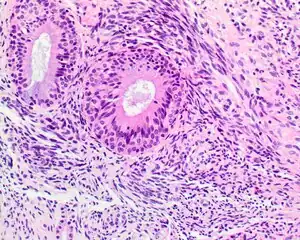

| A high-power view of a hematoxylin- and eosin-stained slide showing respiratory epithelial inclusions within a spindled cell neoplasm showing characteristics of a biphenotypic sinonasal sarcoma | |

- Infiltrative, highly cellular spindled cell neoplasm is poorly circumscribed and unencapsulated. Bone destruction or invasion is common. The cells show medium to long fascicles (nerve fibers), with a herringbone pattern. The cells are remarkably uniform with elongated nuclei. Delicate strands of intercellular collagen without ropy or dense deposition are seen. A very characteristic concurrent surface-type respiratory epithelial proliferation is found from the surface or in small cystic spaces around the cancer cells, often forming glands. The background may have a rich vascularity and usually has a small number of scattered lymphocytes. Extra growths or mitoses are rare, while necrosis, ulceration, and hemorrhage are usually absent.